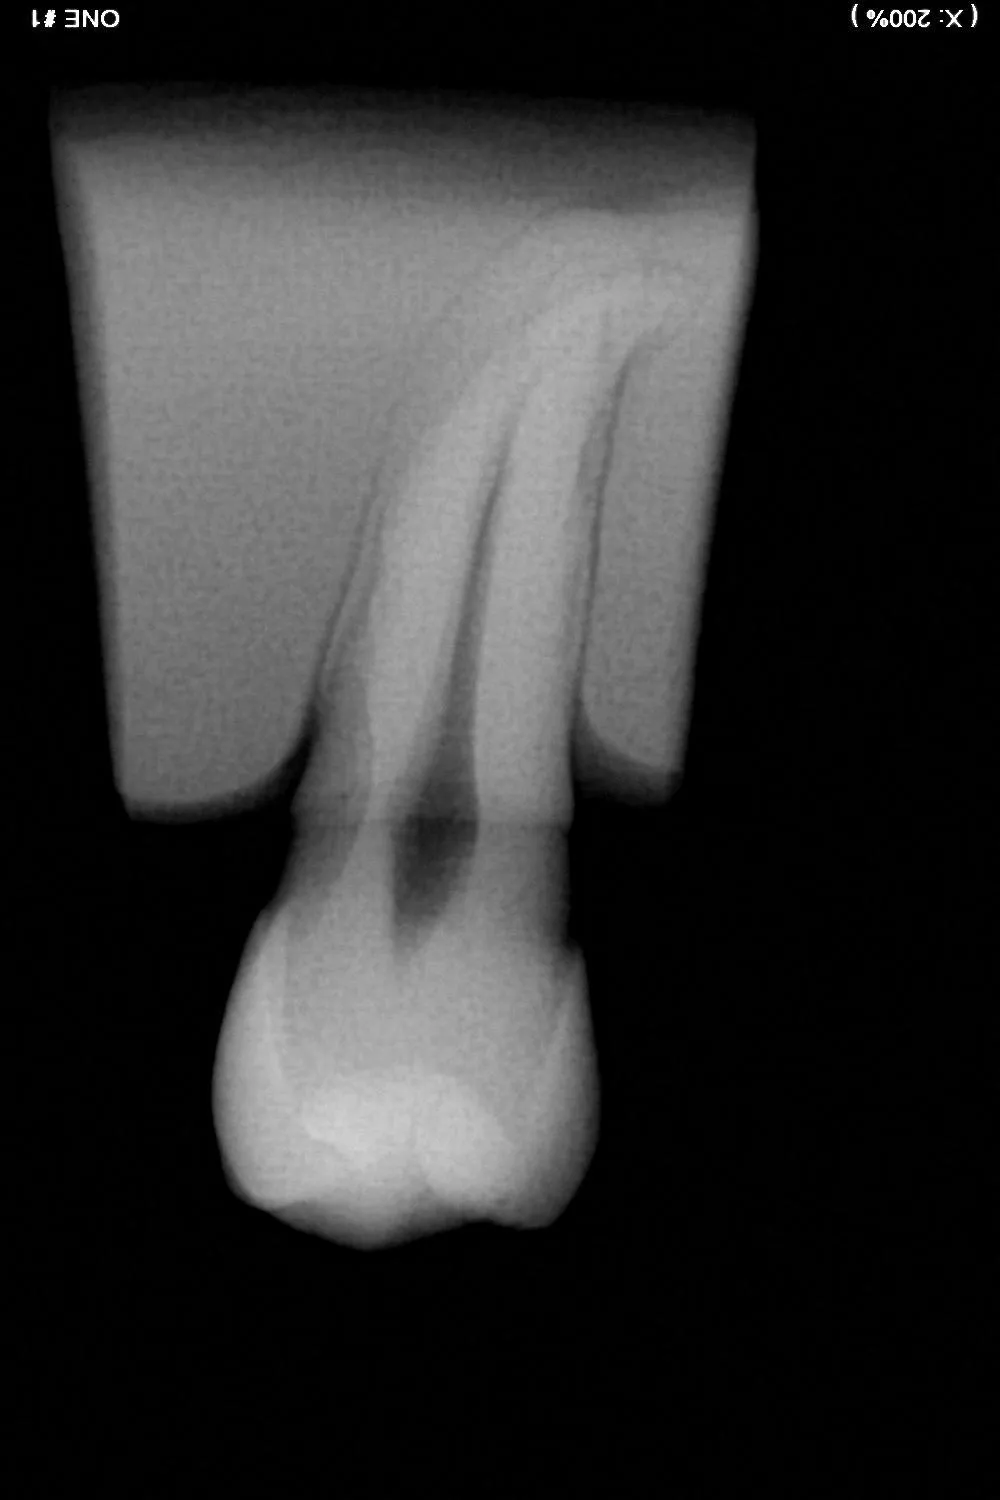

Le traitement endodontique vise à retirer la pulpe infectée, à nettoyer et désinfecter en profondeur les canaux radiculaires, puis à les obturer hermétiquement. Ce protocole minutieux, réalisé sous anesthésie locale, permet dans la majorité des cas d’éviter l’extraction, de soulager la douleur et de restaurer la dent sur une base saine.

Pour traiter l’infection, l’endodontiste doit accéder à la pulpe. Pour ce faire, il placera une digue autour de la dent, c’est un champ qui protège le site en cours de traitement, de la salive et de la langue, pour permettre une désinfection optimale de votre dent. Une ouverture est pratiquée sur la dent afin d’atteindre les canaux. Les tissus infectés sont alors retirés, puis les canaux sont soigneusement nettoyés à l’aide de limes K manuelles et de limes mécaniques type Protaper Gold et Reciproc, ainsi que d’une bonne irrigation des canaux à l’aide de plusieurs solutions désinfectantes (NaClo, EDTA, Chlorhexidine, sérum physiologique). Après séchage, les canaux sont obturés de manière étanche pour prévenir tout risque de recontamination par des bactéries. En fonction de l’état de la dent, une restauration adaptée est ensuite réalisée : soit une obturation classique, soit une couronne si la structure est fragilisée.

Parfois, une dent déjà traitée peut présenter une nouvelle infection. Un retraitement endodontique permet alors de réintervenir sur les canaux pour les assainir et restaurer durablement la dent.